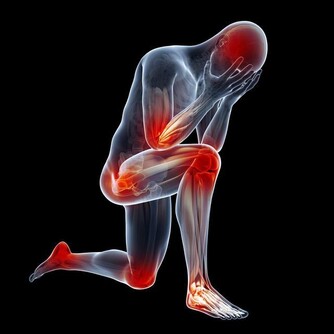

30歲開始,關節痠、痛、軟!

關節退化,是免不了的老化過程。

運動過度、關節受傷、過度肥胖等,都會使關節提早退化,

而膝關節、髖關節、脊椎等,是最容易退化的關節部位。

人類自出生以來,關節軟骨就持續進行著新陳代謝。

16歲前,新生骨頭的速度比退化來得快;

16~18歲時,骨頭的新生與退化速率達到平衡;

年過30歲,由於經年累月所造成的磨損,就逐漸走向退化之路;

60歲以上可說是退化性關節炎的高峰期。

但若運動過度、關節曾受傷或過度肥胖,關節則會提早老化。

像田徑(跑、跳運動)選手,常會有膝關節提早耗損的問題;

體操選手,則是有脊椎提早退化現象。

退化性關節炎依造成原因可分為:原發性退化性關節炎(以老化及肥胖為主因),

及續發性關節炎(包括因受傷所造成的骨折等、遺傳性疾病、代謝性疾病、先天性關節發育異常等)。

臨床上也發現,退化性關節炎存在一些危險因子,

除了年齡及肥胖、外傷之外,女性、感染、反覆的職業傷害、神經肌肉疾病等,

都是高危險族群,應該提高警覺。